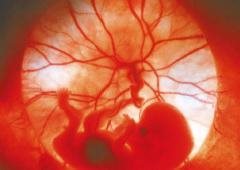

A developing foetus with the placenta visible behind

A developing foetus with the placenta visible behind (Reprinted by permission from Macmillan Publishers Ltd: Nature 419:106-107 by J. Knight, copyright (2002)).

His joint work with Professor Oliver Jensen (Manchester), Professor Ian Dryden and Dr Lopa Leach (Nottingham) involves the development of novel mathematical models and techniques to examine the way the placenta functions during pregnancy. The placenta is an organ we all depend on at the beginning, and which is a root of our life-long well-being. More importantly and tragically, sometimes apparently normal pregnancy results in a condition called pre-eclampsia that endangers both the mother and the baby, and which is attributed to a placental malfunction. The major puzzle of the human placenta is how to connect its tiny microscopic features with effective organ-wide delivery of oxygen and nutrients, something which Dr Chernyavsky has aimed to help address. The models he is developing could bring computer-assisted diagnostics and treatment of placental disorders a step closer.